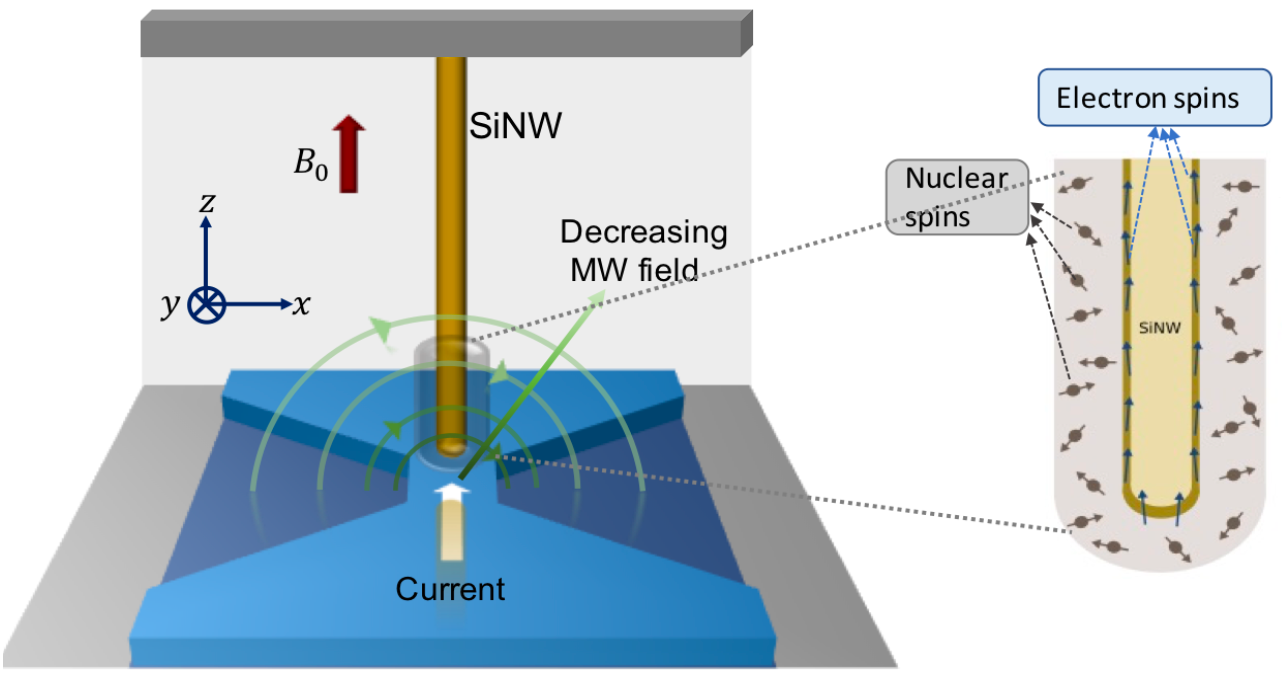

Nanometer-scale MRI opens the door to viewing virus nanoparticles and proteins

MRFM imaging device under microwave irradiation (inset: ultra-sensitive mechanical oscillator — a silicon nanowire, with sample coated at the tip (credit: R. Annabestani et al./Physical Review X)

A new technique allows for magnetic resonance imaging (MRI) at the unprecedented resolution of 2 nanometers — 10,000 times smaller than current millimeter resolution.

It promises to open the door to major advances in understanding virus particles, proteins that cause diseases like Parkinson’s and Alzheimer’s, and discovery of new materials, say researchers at the University of Waterloo Institute for Quantum Computing.

The breakthrough technique combines magnetic resonance force microscopy (MRFM) with the ability to precisely control atomic spins. “We now have unprecedented access to understanding complex biomolecules,” says Waterloo physicist Raffi Budakian. — Waterloo, Physical Review X, arXiv (open-access)